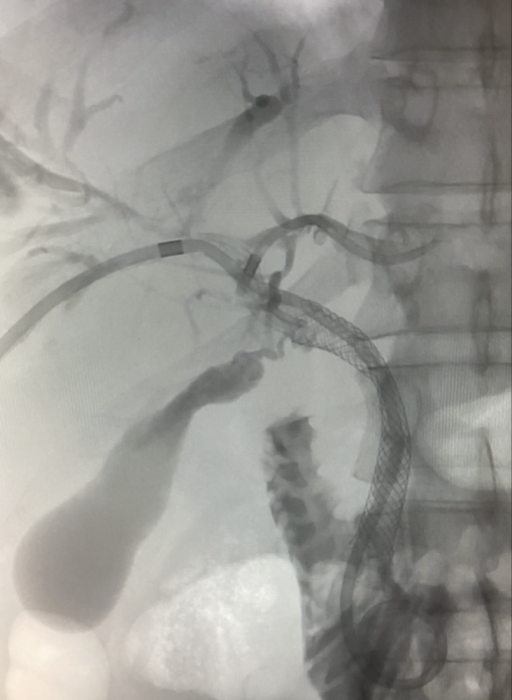

Colocación de comunicación transyugular portosistémica (TIPS).